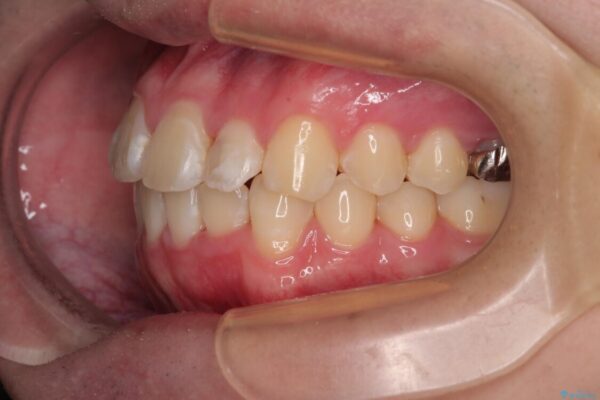

このような歯列の狭さに起因するデコボコを改善するために、**MARPE(骨に固定する上顎急速拡大装置)**を使用して、上顎の横幅を拡大し、これにより歯が並ぶためのスペースを確保し、メタルブラケットを用いて歯列を整えていく計画としました。

費用面を考慮し、装置はコストパフォーマンスに優れたメタルブラケットを選択。見た目よりも機能と効果を重視したい方には特におすすめの選択肢です。

治療途中

• 1年でここまで変わる!歯列のがたつきと正中のズレを改善した矯正治療(メタルブラケット×MARPE) 治療途中画像